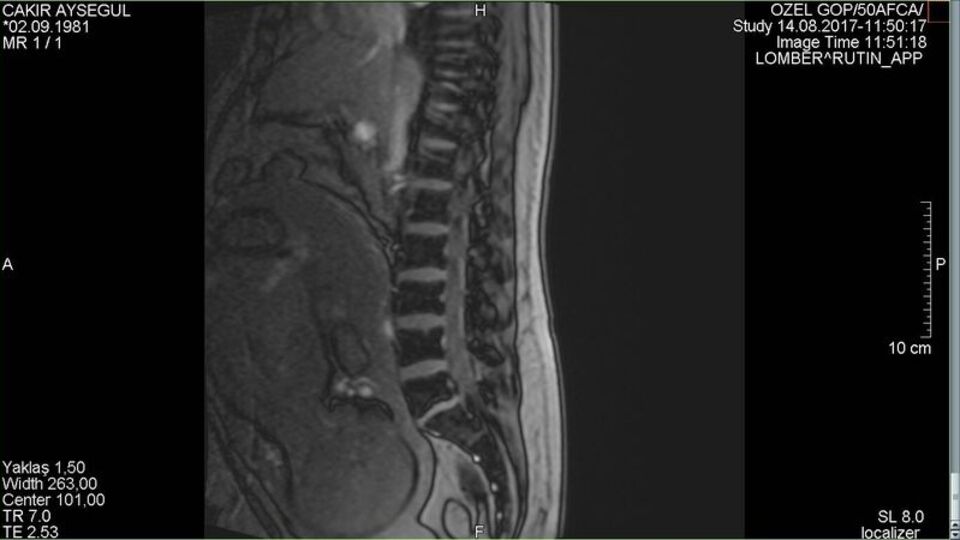

Kocaeli'nde yaşayan 36 yaşındaki Ayşegül Çakır 8 aylık hamileyken bel fıtığı patladı. Dayanılmaz ağrılar nedeniyle uyuyamadığını söyleyen 1 çocuk annesi genç kadın tedavi olmak için hastaneye başvurdu. DHA'nın haberine göre; fıtığının çok ilerlemesi nedeniyle ameliyat olması gerektiği söylenen Çakır, 10 binde 1 gibi az bir oranda yapılan ameliyatla fıtığından kurtuldu. Normal şartlarda yüzü koyun yatırılarak ameliyat edilmesi gereken genç kadın hamilelik nedeniyle yan yatırılarak ve genel anestezi altında ameliyat edildi. Ameliyatın ardından ilk defa rahat uyuduğunu belirten Çakır'ın hamileliği devam ederken kendisinin ve bebeğinin sağlığının iyi olduğu tespit edildi. Doç. Dr. Mete Karatay ve Yrd. Doç. Dr. İdris Sertbaş tarafından gerçekleştirilen operasyon 1 saat içinde tamamlanarak anne ve bebeğin gereksiz yere anestezi almaması sağlanmış oldu.

Bel fıtığı patlamış şekilde başvuran hastanın operasyonunu gerçekleştiren Doç. Dr. Karatay hastanın durumu ile ilgili şunları söyledi: "Hastamız 36 yaşında, 8 aylık hamile bir kadın. Bel ağrısı şikayetleri var. Gebelik öncesinde de bel fıtığı başlangıç tanısı koyulmuş. Gebelerde yüzde 50 oranında zaten bel ağrısı görüyoruz. Şiddetli bel ağrısı daha sonra ilerleyici semptomatik dediğimiz bel fıtığı noktasına gitmesi genellikle nadir görülür ama bu hastamızda sonucu güzel oldu. Ameliyatlık bir bel fıtığı olduğu için bize başvurdu. Hikayesinde istirahat ettiği, ilaç tedavisi gördüğü ama şikayetlerinin düzelmediğini anladık. Yaptırdığımız MR tetkikinde halk arasında patlamış dediğimiz ilerleyici bir bel fıtığı saptamamız üzerine kadın doğum ve anestezi hekim arkadaşlarımızla görüşerek hastamızın ameliyatını gerçekleştirdik. Ameliyatımız gayet başarılı geçti. Genel anestezi ile yapıldı. Özel bir cerrahi pozisyonda yapıldı. Anestezi açısından bebeğe hiç zarar verilmeyecek şekilde hızlı bir cerrahi ile ameliyatımız sonlandırıldı. Ameliyat sonrasında hastamız ilk defa güzel bir uyku uyuduğunu ifade ederek bir gece yattıktan sonra taburcu oldu."